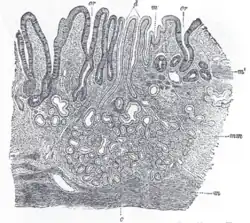

The GI tract is essentially a hollow tube connecting the mouth to the anus. The GI tract has a similar layout through out its length:

- An inner mucosal layer with an epithelial lining

- A submucosal layer

- A thin layer of muscle , the Muscularis Mucosa is at the junction of the mucosal and sub mucosal layers, outside this are the nerves of the mucosal plexus

- A muscular layer with an inner circular muscle layer and an outer longitudinal layer

- Between the muscles are the nerves of the myenteric plexus

- A serosal layer which is continuous with the mesentry

This is illustrated graphically here:

The mucosal layer consists of an epithelial layer, and its underlying supportive tissue, the Lamina Propria. It is separated from the submucosal layer by the Muscularis Mucosa. The epithelial layer varies from section to section of the gut. In the oesophagus it is a non-cornified stratified squamous epithelium; in the stomach it is mainly mucosal cells; the small intestine and large intestine are characterized by absorptive cells, with many mucous producing goblet cells. In the absorptive sections of the intestine, the surface are for absorption is greatly increased by finger-like projections into the lumen called villi, and the absorptive cells themselves also have small projections of microvilli, giving them the appearance of a brush border when viewed with a light microscope.

The lamina propria contains lymph and blood vessels which drain into larger vessels in the submucosal layer. Also in the lamina propria, particularly in the absorptive layers are numerous immune cells, wandering macrophages and lymphocytes, as well as aggregations of lymphoid tissue called called Peyers patches. By some estimates 80% of the body's lymphoid tissue is in the intestine.

The submucosa consists of connective tissue with larger blood and lymph vessels. It is separated from the mucosa by the muscularis mucosa. Also in the submucosal layer is the submucosal plexus, part of the enteric nervous system. The muscularis mucosa probably acts to propel the contents of the mucosal glandular lumens and crypts (see below) into the lumen and also to enhance contact of the cells with the contents of the lumen.

Consists of an inner circular muscle, and an outer longitudinal muscle. Between the two layers is the mesenteric plexus, also part of the enteric nervous system. In the stomach there is also an oblique layer of muscle fibers interior to these two. The musclar layers work in harmony to produce peristaltic contractions and segmental contractions.

The serosa is a continuation of the peritoneal membrane. It is useful to think of the gut as being envaginated into the peritoneal membrane until it completely surrounds it. The double layer of membrane as it attaches to the gut is called the mesentery, and it contains the main vessels and the non-intrinsic nerve supply to the gut.